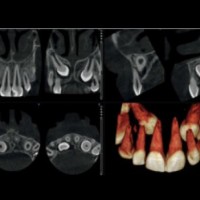

Zubné RTG pracovisko - DENTINIKA

Stomatológia - zubná ambulancia, zubár